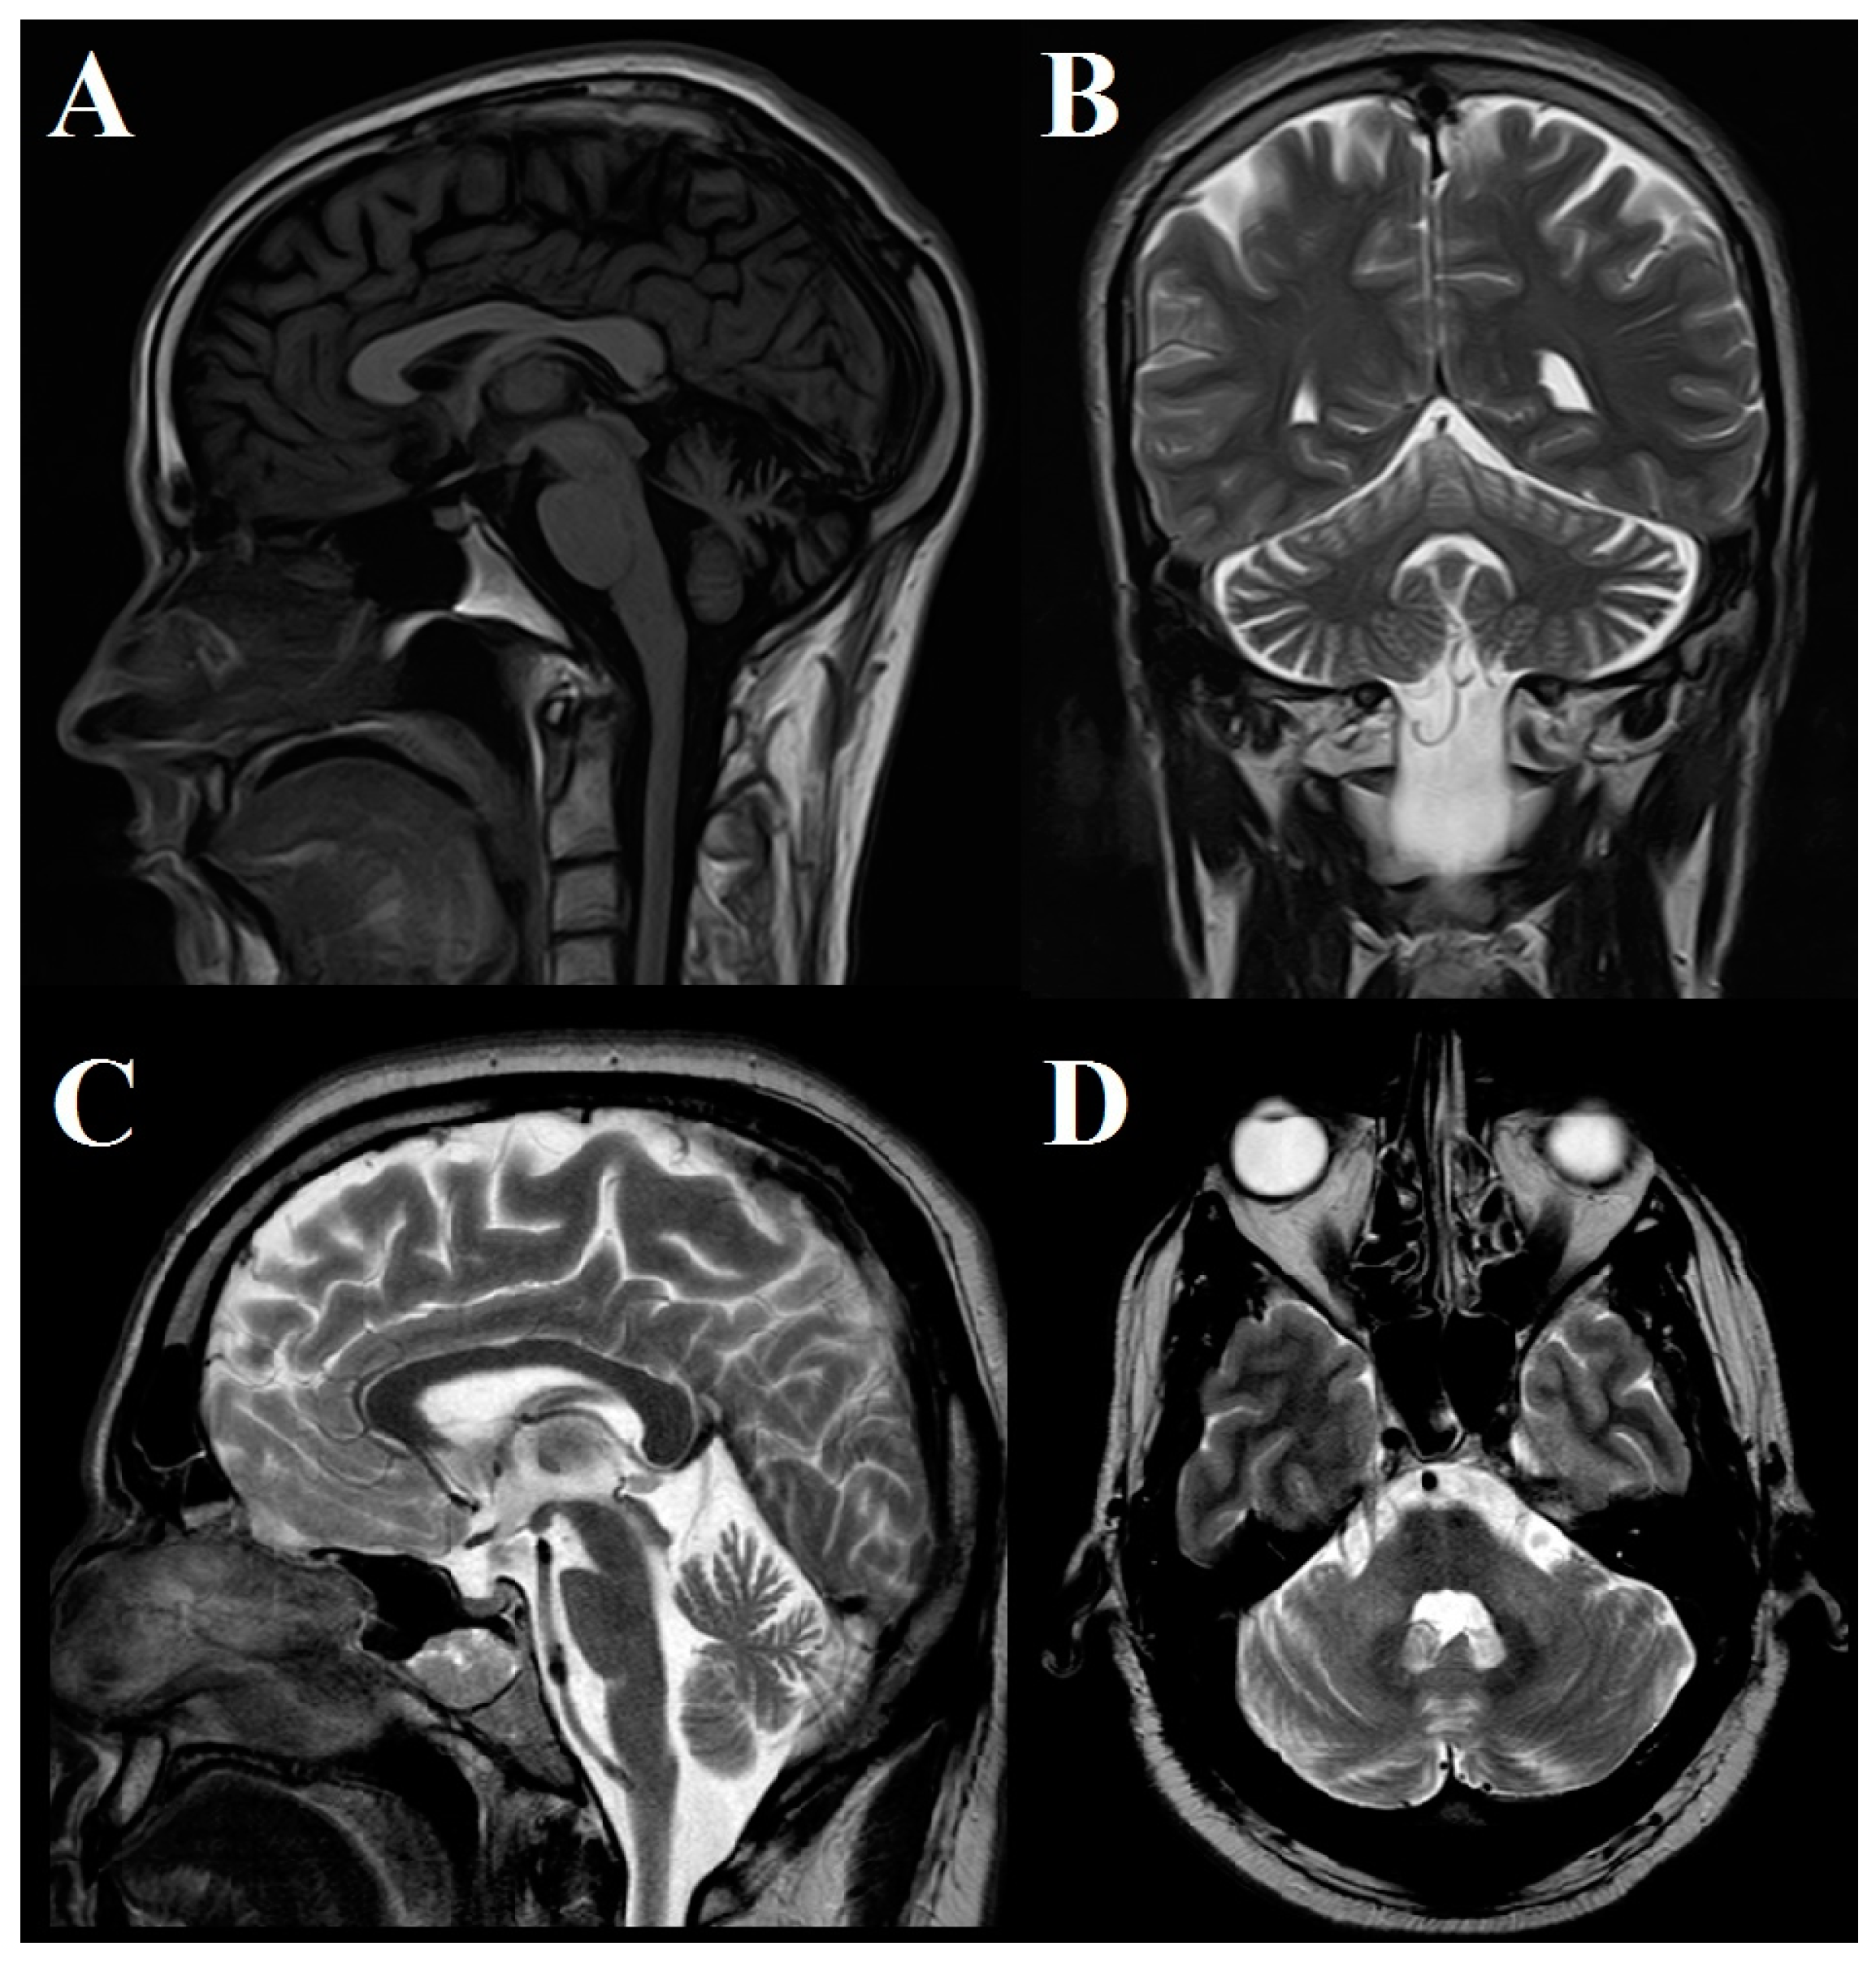

In two patients, brain MRI was normal; in 5 patients, mild to moderate atrophy of the cerebellar hemispheres and vermis was observed; and in 1 case, pontocerebellar atrophy was found (Figure 2).

Figure 2.

Brain MRI study. (A) Saggital T2 FLAIR and (B) coronal T2 images in Patient #5 show moderate cerebellar atrophy involving both hemispheres and anterior and superior vermis. (C) Sagittal and (D) axial T2 images in Patient #7 show moderate cerebellar and brainstem atrophy.

Brain MRI study in SCA27B often shows isolated cerebellar atrophy predominantly in the vermis, as observed in our cases [15]. Nevertheless, in some patients, cerebral MRI is normal, without signs of cerebellar hemispheric or vermis atrophy [9,13]. In sporadic cases with sudden onset of ataxia, vertigo or diplopia, and normal cerebral MRI, it is necessary to suspect immune-mediated ataxias, especially cerebellar ataxia with glutamic acid decarboxylase antibodies [31].